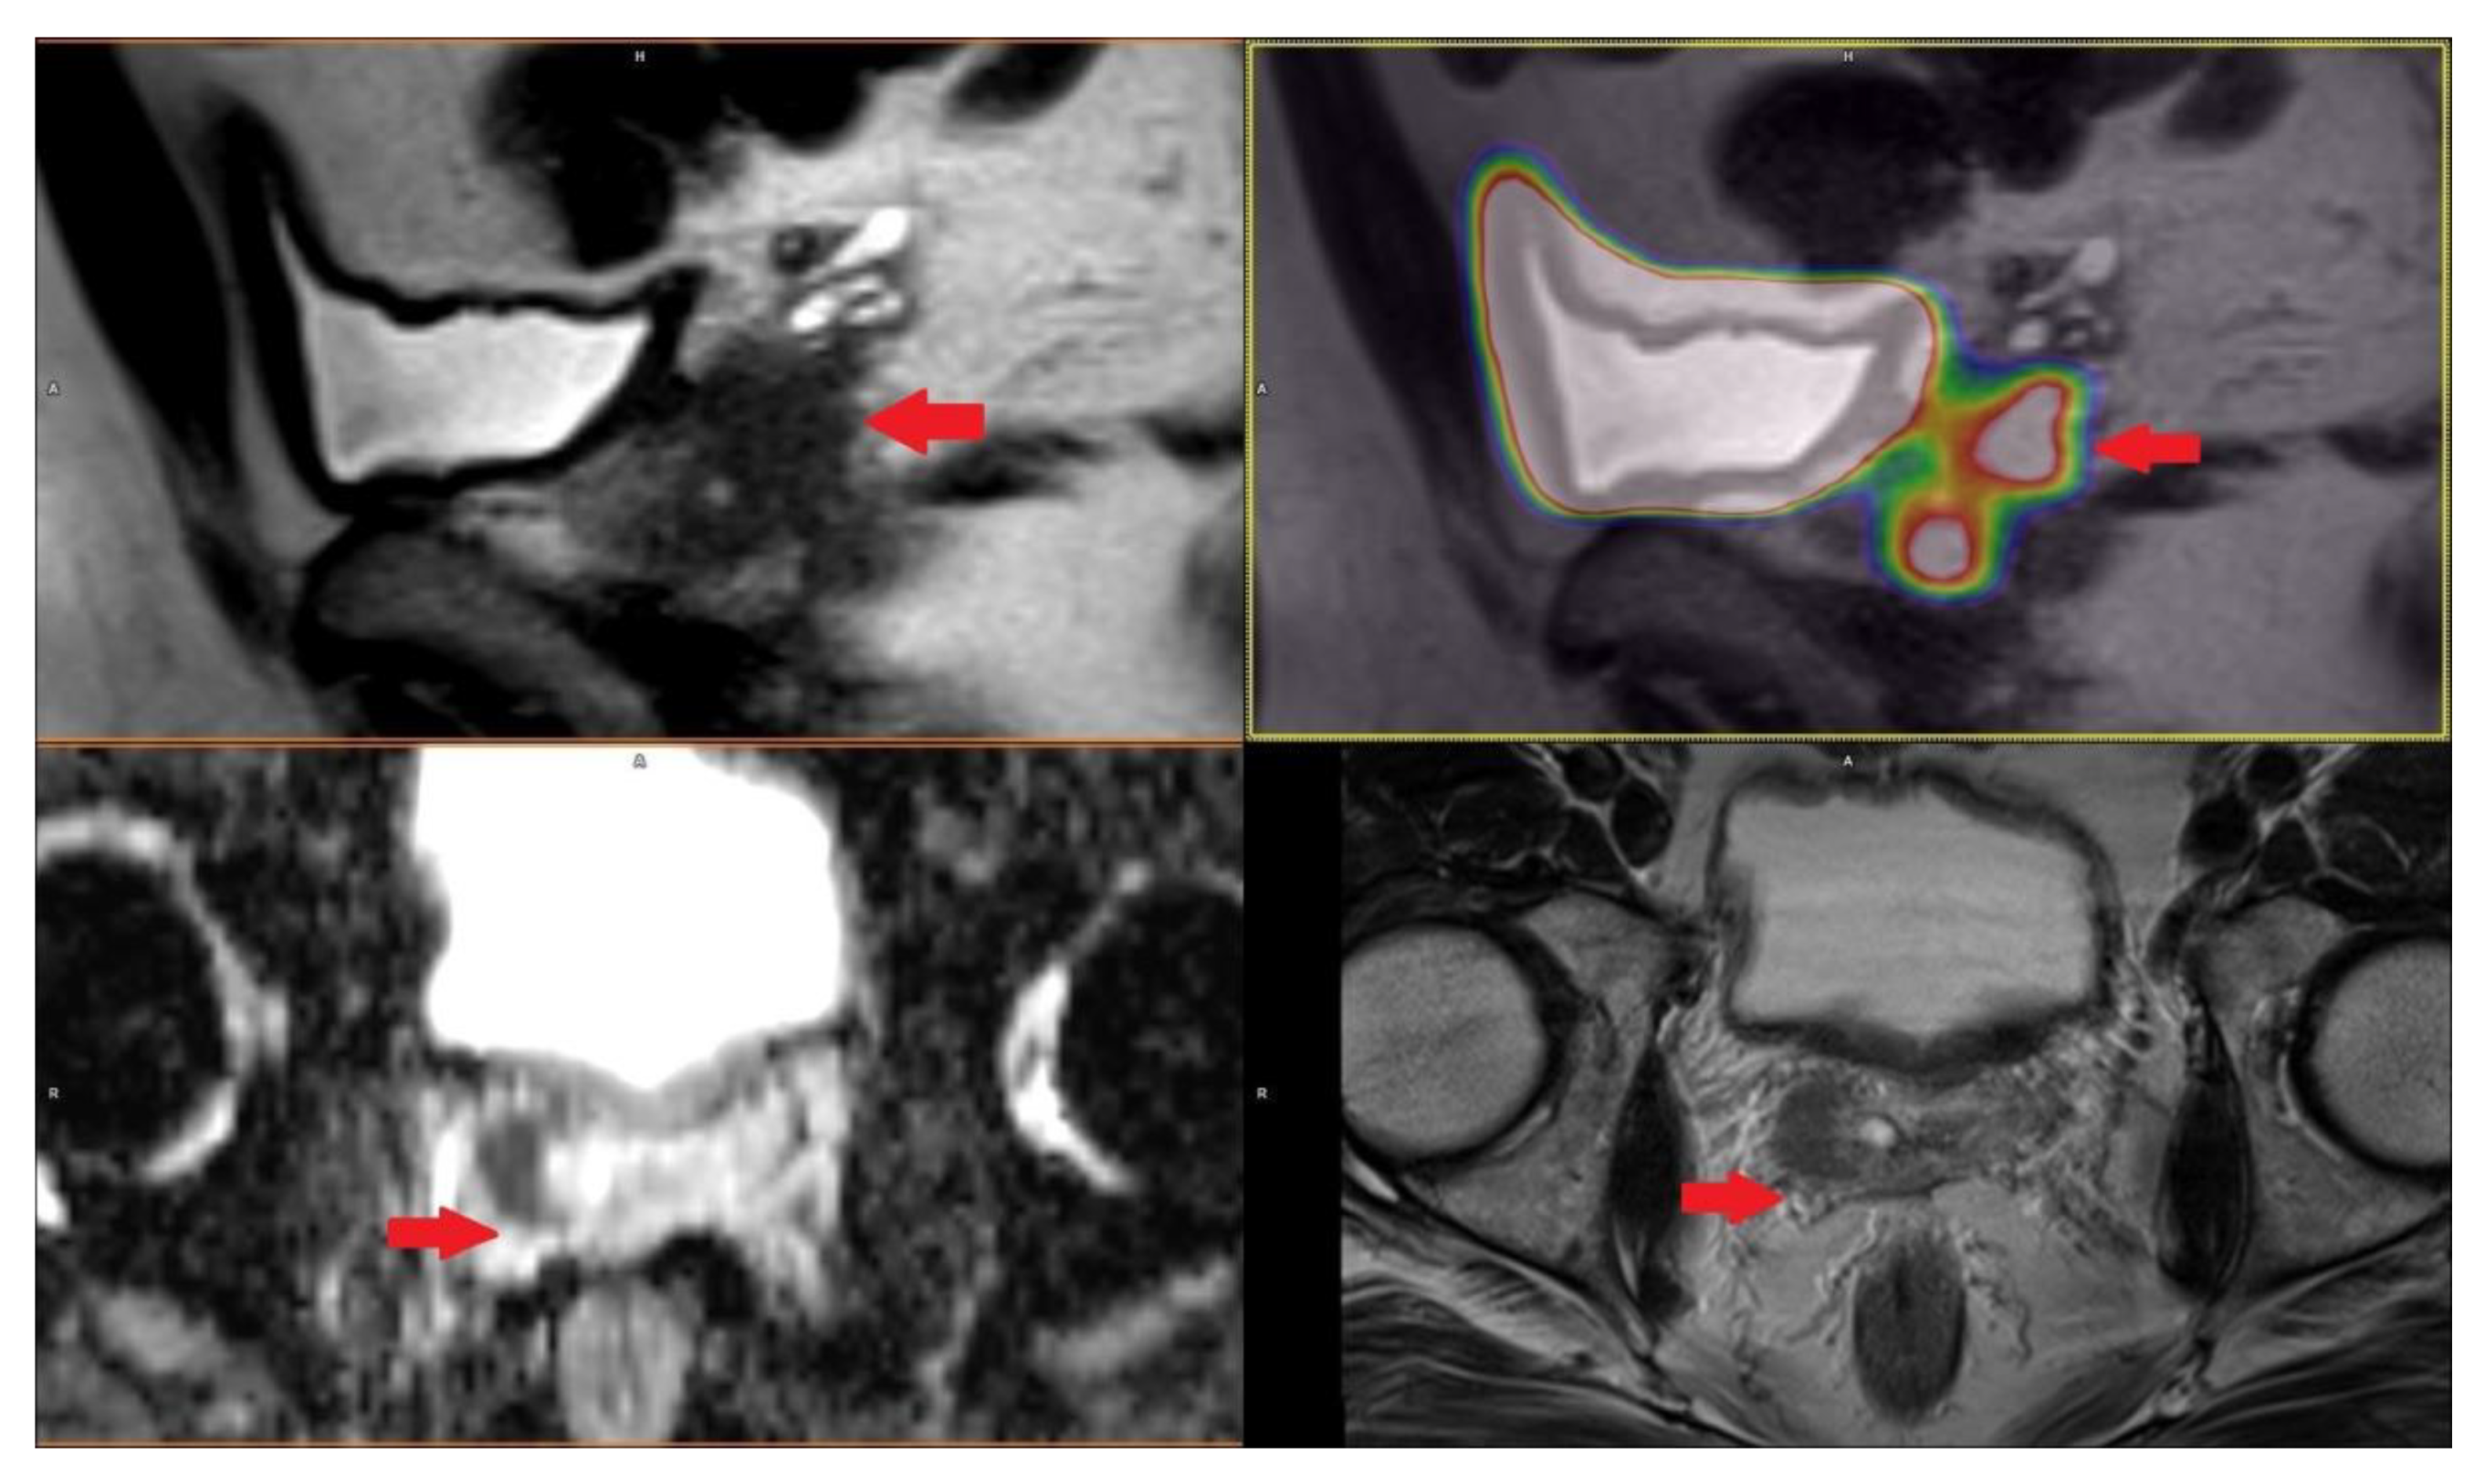

2.4. The Key Role of Imaging Techniques in Staging and Surgical Navigation